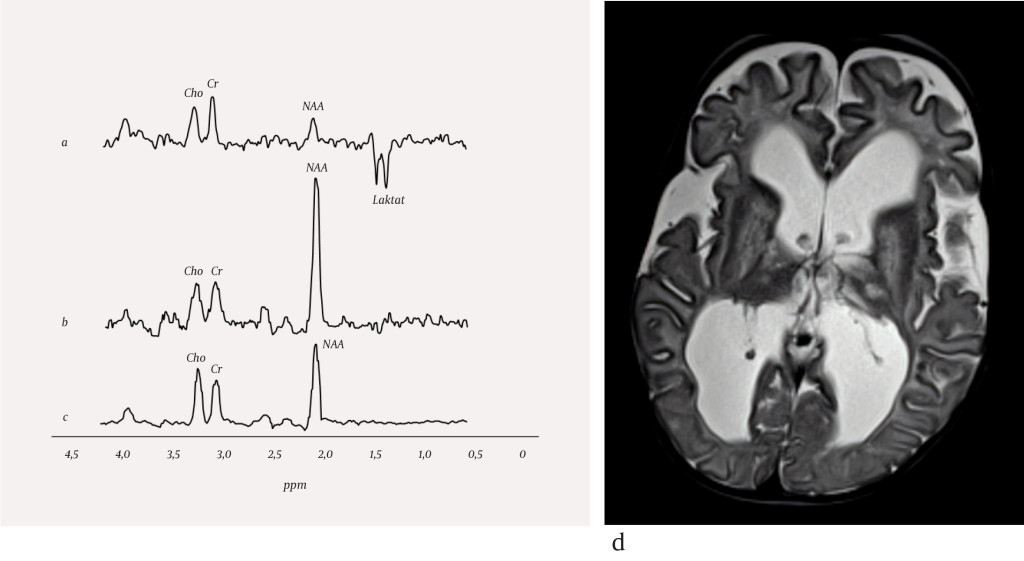

Figure 3 Chemical shift imaging of glioblastoma: a) contrast-enhanced T1-weighted image, showing the volume specified for…

Figure 3 Chemical shift imaging of glioblastoma: a) contrast-enhanced T1-weighted image, showing the volume specified for chemical shift imaging, and b) choline map from chemical shift imaging showing the choline level in the volume for spectroscopy. The colour chart illustrates the choline level, from low (blue) to high (red), and in this example, high levels of choline (red) can be seen in the medial portion of the glioblastoma.